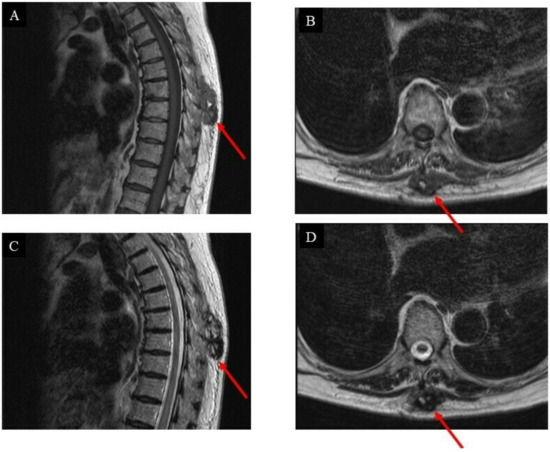

2. Case Presentation